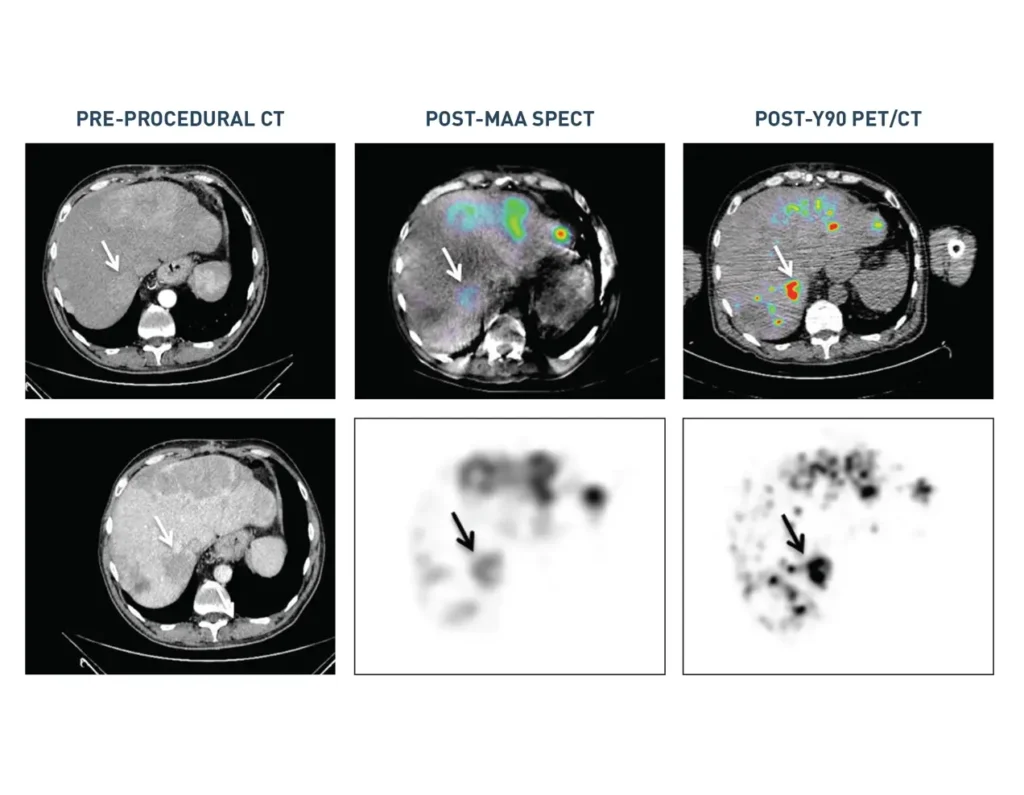

- Pasciak AS, McElmurray JH, Bourgeois AC, Heidel RE, Bradley YC. The impact of an antireflux catheter on target volume particulate distribution in liver-directed embolotherapy: a pilot study. J Vasc Interv Radiol. 2015;26(5):660-669.